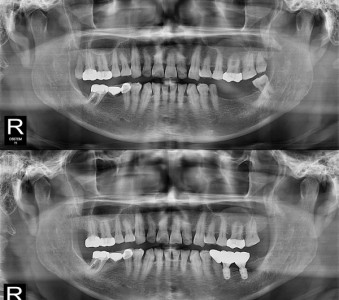

以成果证明实力。

国际摩牙齿科

真实临床案例